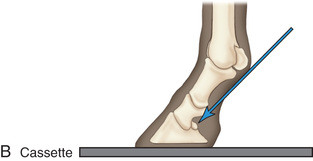

Digit/foot: P-III (distal phalanx, coffin bone) P-II (middle phalanx) P-I (proximal phalanx-pastern) Proximal interphalangeal joint (pastern joint) joint | DP (Standard) (Fig. 24.62B,C) | Dorsal 45-degree proximal–palmarodistal (D45Pr-PaDi) | Foot slightly forward on image receptor. | Perpendicular to foot axis at MSP (midsagittal plane) at area of interest with beam angled ~45 degrees to ground |

| Lateral (Standard) (Fig. 24.62D) | Lateromedial | On a block to elevate limb for P-III; resting on ground for other views. | 90 degrees lateral to MSP, parallel to ground on area of interest: coronary band for PIII | |